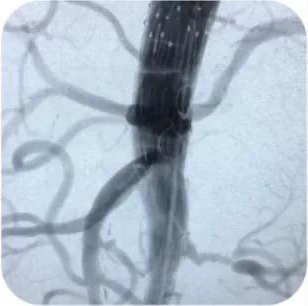

缜密的手术方案

经过周密细致的术前准备,在吴学君的现场指导下,董典宁带领主治医师高培显、主治医师孔祥骞、医师李刚在东院复合手术室,利用体外预开窗技术为患者进行慢性包裹性破裂腹主动脉瘤腔内修复术。手术顺利完成,术中各内脏血管都得到满意重建,术中失血约200ml,术中、术后均未出现肝脏、脾脏、肠道、双肾、下肢缺血及血管破裂出血等严重并发症。患者目前已康复出院。

各内脏血管得到满意重建